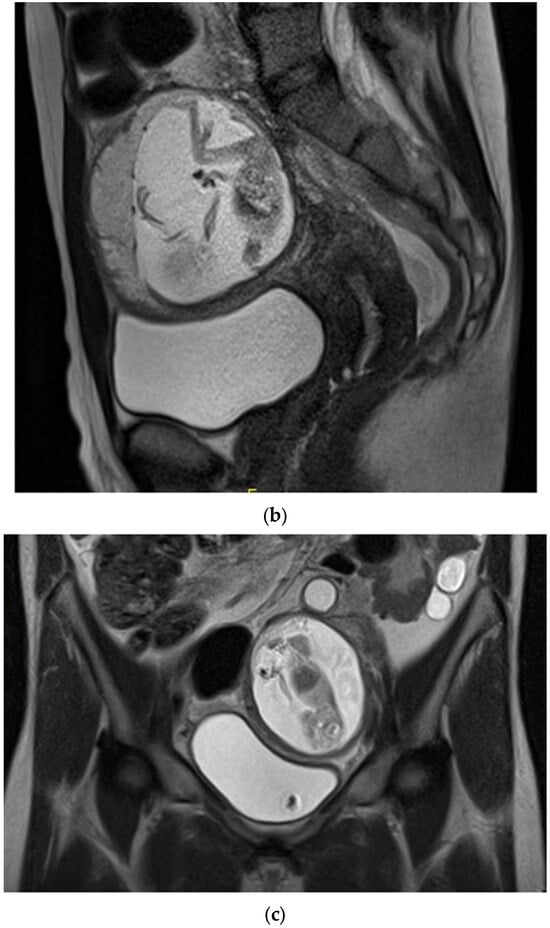

Figure 2.

MRI without contrast showed that the ectopic gestational sac exerted mass effect upon the uterus and bladder, and was associated with a moderate amount of pelvic fluid. (a) Axial T2 HASTE demonstrating ectopic pregnancy in the left adnexa with associated mass effect on the bladder and uterus which deviate to the right. The placenta is located anteriorly within the gestational sac. (b) Sagittal T2 HASTE demonstrating ectopic pregnancy located anterior to uterine fundus and superior to bladder. The anterior wall of the gestational sac is located approximately 1.3 cm deep to the overlying skin surface. There is a moderate amount of complex free pelvic fluid. (c) Coronal T2 HASTE demonstrating intact gestational sac superior to the bladder in the left adnexa. The left ovary is partially visualized superior to the gestational sac and contains an incidental 2.0 cm follicle.